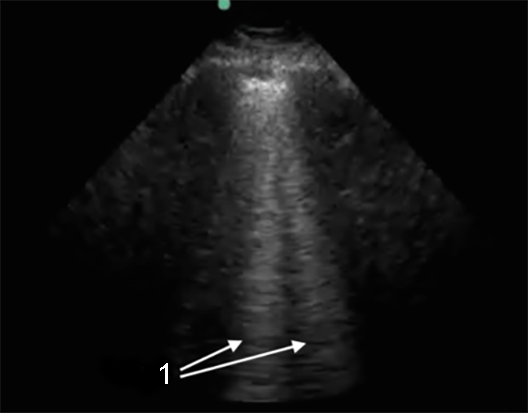

Lung B-Lines Image

B-Lines